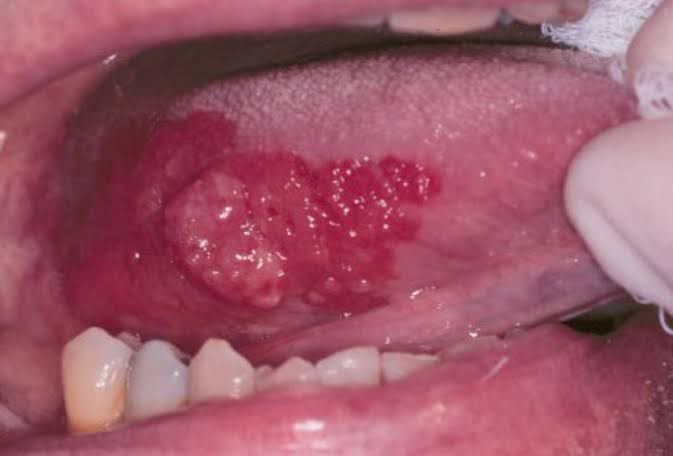

Erythroplakia is a velvety, red coloured lesion of mucous membrane which may be flat or depressed when compared to the surrounding area. This lesion is associated with risk of malignancy. Risk factors for this lesion are smoking, chewing tobacco and cigars. Picture credits: http://www.exodontia.info/Erythroplakia_Erythroplasia.html